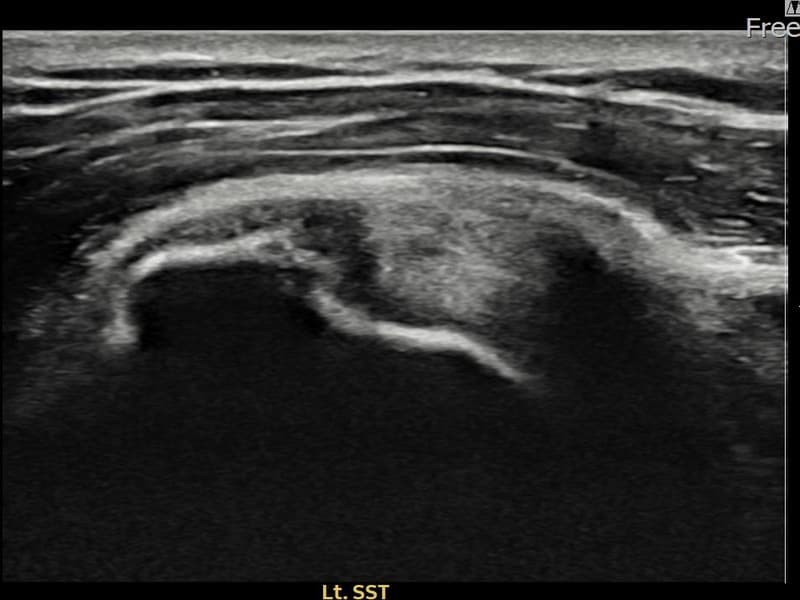

Before

시술 전 초음파 측정 결과 파열 크기는 7mm × 3mm (힘줄 두께의 약 30% 결손)로 확인되었습니다. 시술 전 초음파에서 좌측 극상근건 내 에코 단절과 힘줄 결손 소견이 확인되었습니다. 시술 후 8개월 추적 초음파에서 파열 부위에 재생 조직이 완전히 채워지고 힘줄 에코 패턴이 정상화된 것이 관찰되었습니다.

50대 중반 남성 환자분으로, 좌측 어깨 통증이 오래 지속되었으나 바쁜 일상으로 치료를 미루시다가 통증이 악화되어 내원하셨습니다. 초음파 검사에서 좌측 극상근건 부분파열이 확인되었으며, 초음파 유도 하 축소봉합술을 시행하였습니다. 이 환자분의 경우 시술 후 8개월 간격의 장기 추적 초음파를 시행하였는데, 파열 부위가 완전히 재생 조직으로 채워지고 힘줄 구조가 정상화된 우수한 결과를 보여주셨습니다. 현재 통증 없이 정상 생활을 하고 계십니다.